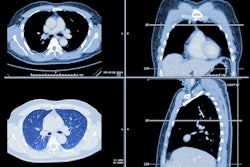

The NeuViz Epoch 512-slice CT scanner incorporates artificial intelligence (AI) technology. Organ-specific AI algorithms identify anatomy for precise scanning and optimize patient scans based on their anatomy. Iterative reconstruction software and 60 kV scanning also reduce patient dose, Neusoft noted.